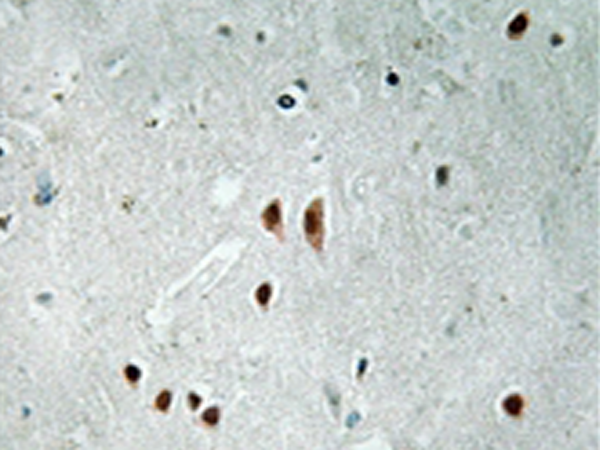

Applications: |

IHC |

IHC positive control: |

Human brain tissue |

IHC Recommend dilution: |

50-100 |